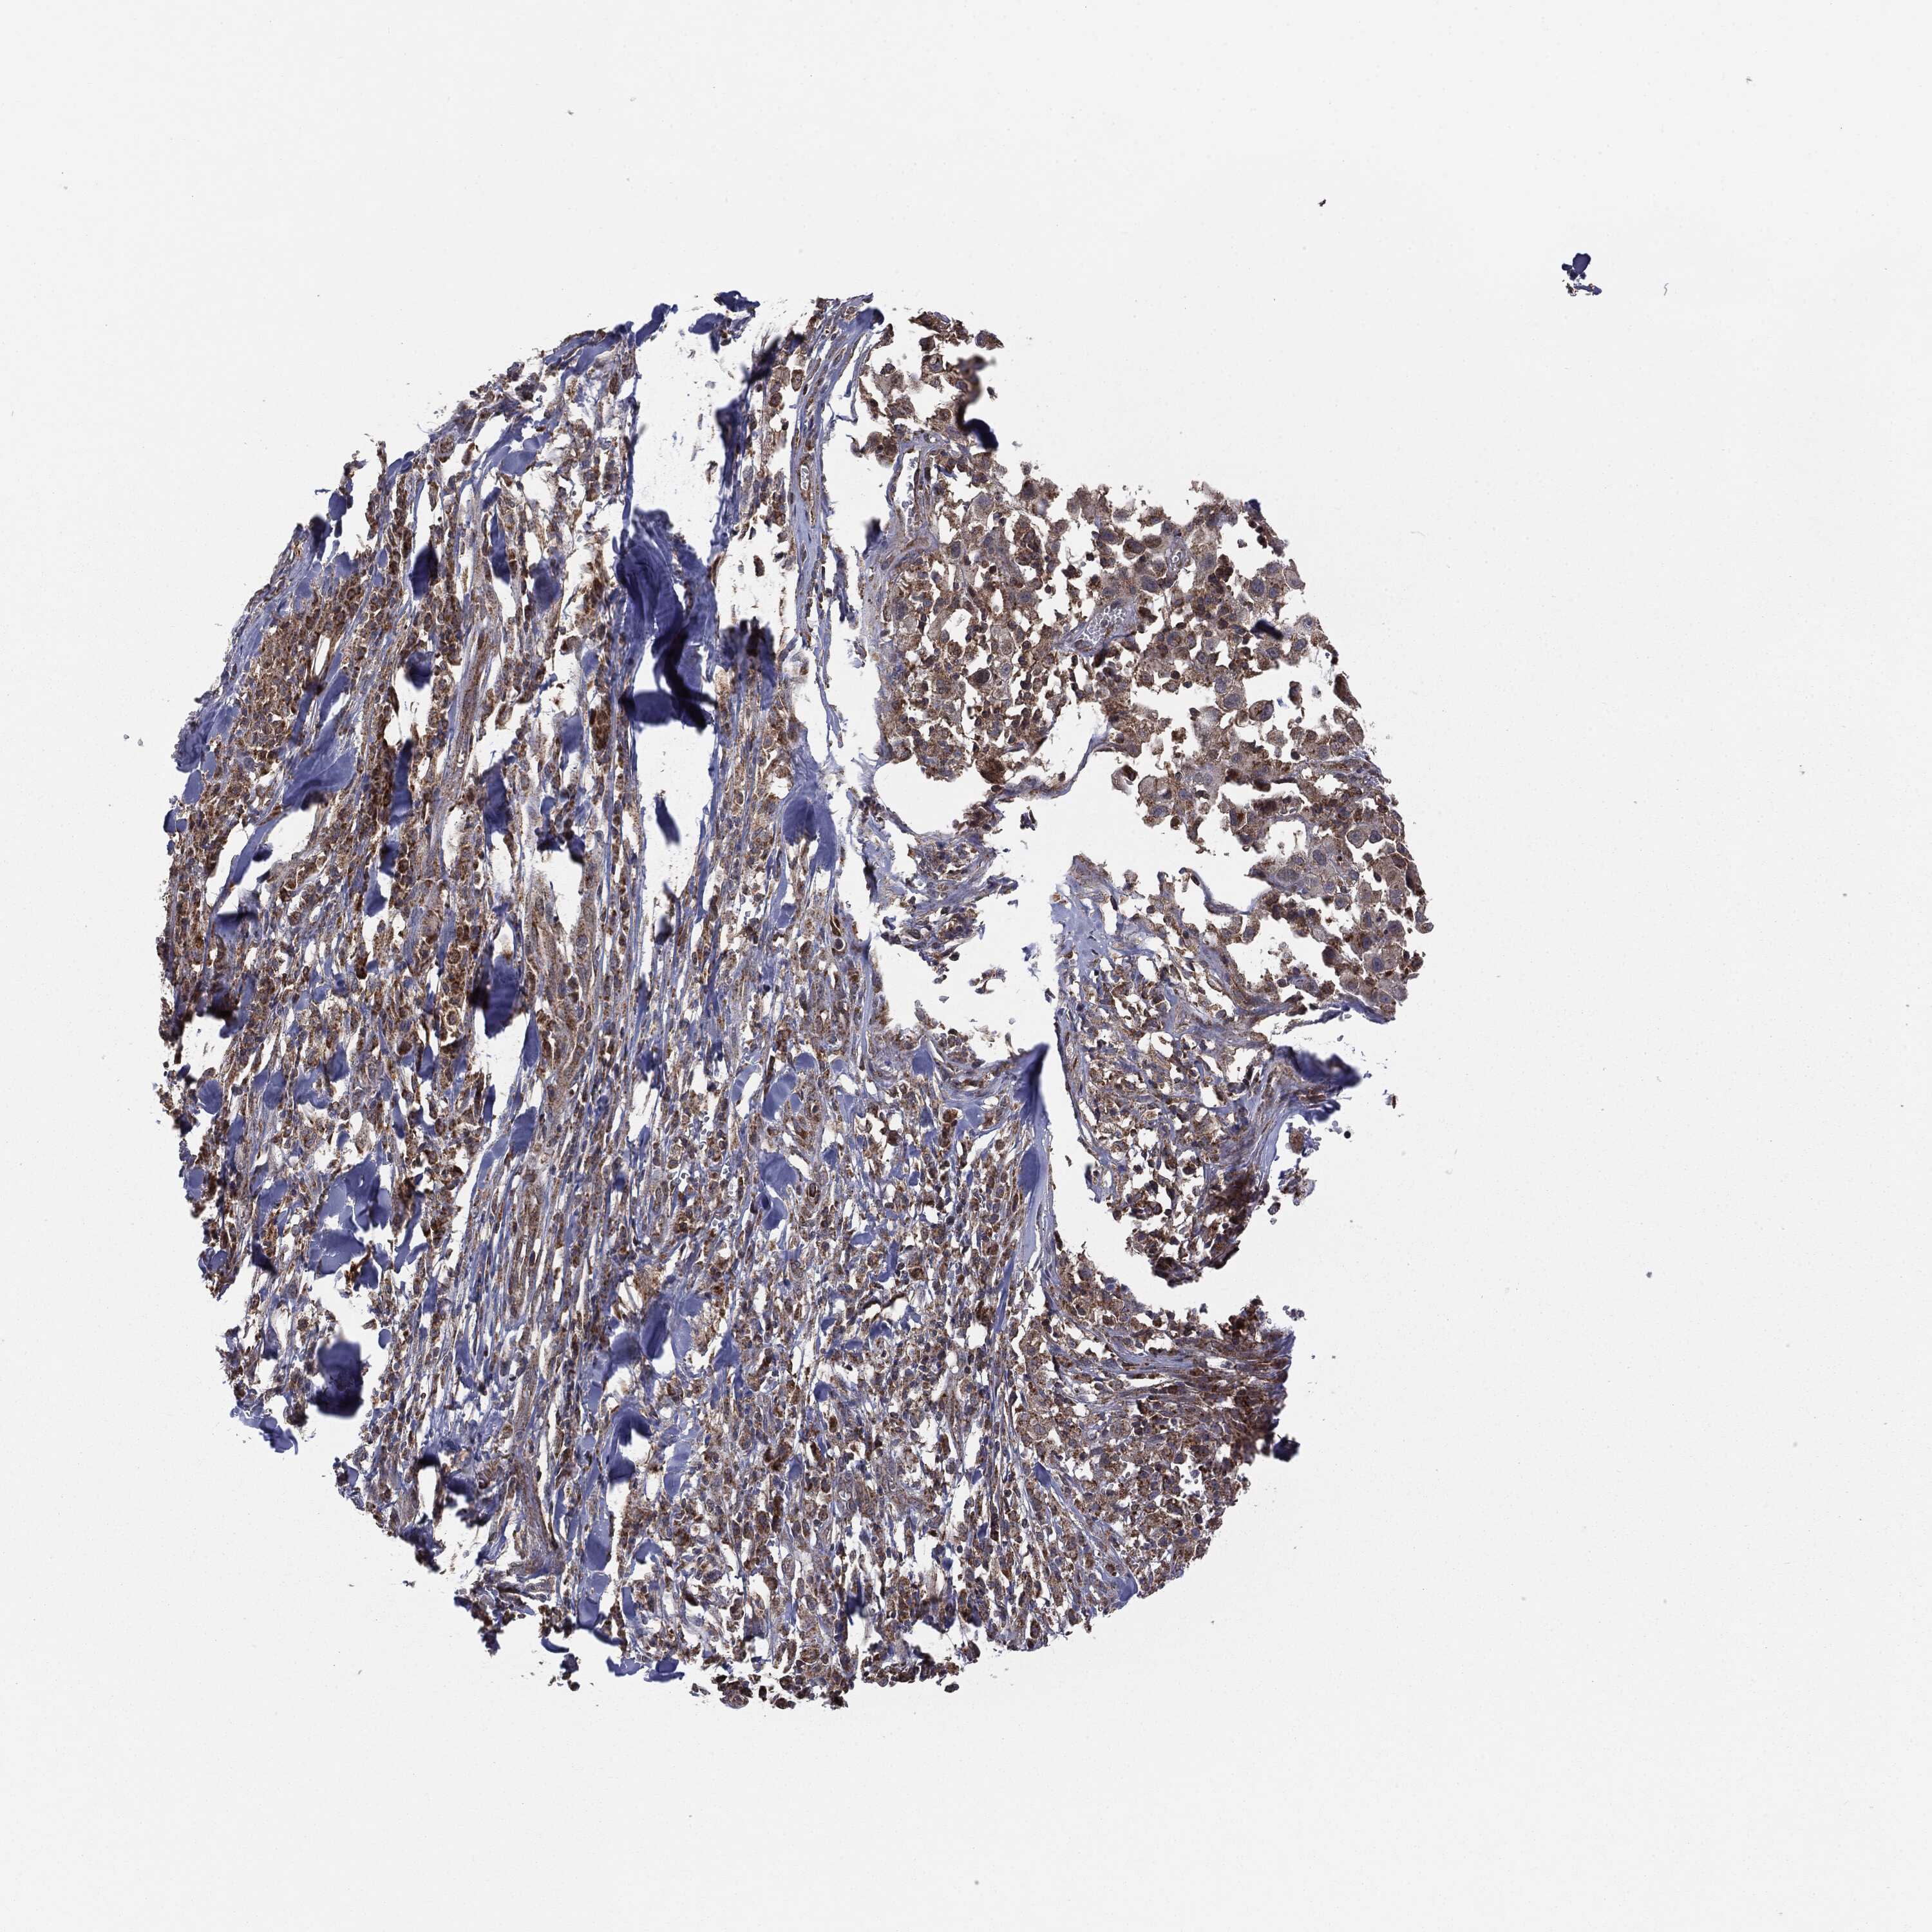

MELANOMA - Protein expressioni

A mouse-over function shows sample information and annotation data. Click on an image to view it in a full screen mode. Samples can be filtered based on level of antibody staining by selecting one or several of the following categories: high, medium, low and not detected. The assay and annotation is described here.

Note that samples used for immunohistochemistry by the Human Protein Atlas do not correspond to samples in the TCGA dataset.

Antibody stainingi

Antibody staining in the annotated cell types in the current human tissue is reported as not detected, low, medium, or high, based on conventional immunohistochemistry profiling in selected tissues. This score is based on the combination of the staining intensity and fraction of stained cells.

Each image is clickable and will lead to virtual microscopy that enables deeper exploration of all samples and also displays staining intensity scores, fraction scores and subcellular localization as well as patient and tissue information for each sample.

CAB069425

CAB080053

CAB080065

CAB080070

CAB080081

CAB080095

CAB080097

Staining

High

Medium

Low

Not detected

Intensity

Strong

Moderate

Weak

Negative

Quantity

>75%

75%-25%

<25%

None

Location

Nuclear

Cytoplasmic/membranous

Cytoplasmic/membranous,nuclear

Malignant melanoma, NOS

Malignant melanoma, Metastatic site